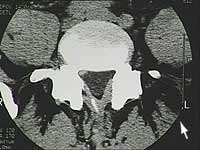

Vous pouvez visualiser sur ce CT l’image d’une hernie discale média latérale.

Hier das Bild einer Computertomographie. Der dreieckige Wirbelkanal, sollte sauber abgegrenzt sein.

Führen Sie Ihren Mauszeiger über das Bild um die mediolaterale Hernie zu sehen. |

Bild 1: kleine linkslaterale Hernie Bild 2: breitbasige Protrusion |

Bild 1: Normale CT. Bei den Hernien-ähnlichen Aufhellungen handelt es sich um die zwei abgehenden Spinalnerven.

Bild 2: Cette hernie par exemple occupe 1/3 du canal rachidien et n’a pourtant pas dû être opérée. |